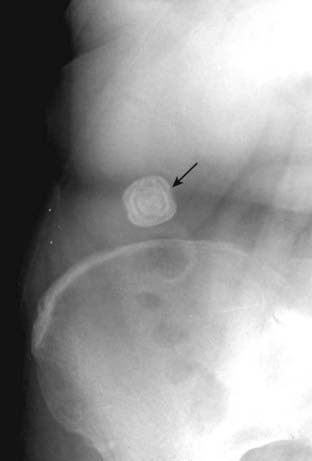

image

Figure 16-7 Renal calculus.

There is a small calcification (solid black arrow) that overlies the shadow of the left kidney (solid white arrow) on this close-up of a conventional abdominal radiograph. Although the stone is too small to recognize lamination, its location suggests a renal calculus. Because of its greater sensitivity, a CT stone search has essentially replaced conventional radiography for the identification of renal and ureteral calculi.